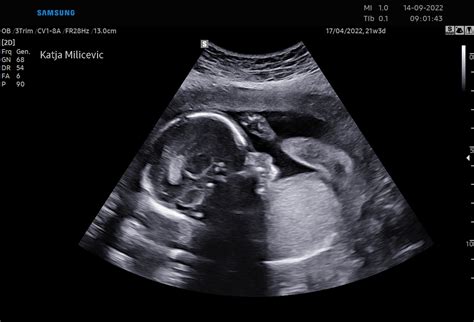

Fetalni Biofizični Profil in Ultrazvočne Meritve

V 35. tednu nosečnosti se lahko izvajajo različni ultrazvočni pregledi, ki ocenjujejo stanje ploda. Pri fetalnem biofizičnem profilu se ocenjujejo dihalni gibi ploda v vzdolžnem ali prečnem položaju, pri čemer se opazuje gibanje trebušne prepone. Če dihalni gibi trajajo 60 sekund v 30 minutah, plod dobi 2 točki; če trajajo 30-60 sekund, dobi 1 točko; če dihalnih gibov ni ali trajajo manj kot 30 sekund, dobi plod 0 točk.

Ocenjuje se tudi količina plodovnice z merjenjem navpičnega najglobjega tekočinskega žepa v maternici. Če je žep globlji od 2 cm, plod dobi 2 točki; če je globok 1-2 cm, dobi 1 točko; če je globok manj kot 1 cm, dobi plod 0 točk. O oligohidramniju govorimo, če je v navpičnem žepu plodovnice manj kot 2 cm; o polihidramnionu pa, če je žep večji od 12 cm. Če je najgloblji žep dolg od 3-8 cm, govorimo o normalni količini plodovnice. Indeks plodovnice (AFI) je seštevek najglobljih žepov v štirih kvadrantih maternice.

Pri pregledu posteljice se ocenjuje njena stopnja zrelosti, ki je lahko 0, I, II ali III. Stopnje zrelosti kažejo na staranje posteljice.

Pomembne so tudi meritve pretokov v popkovnični arteriji s pomočjo barvnega in pulzirajočega Dopplerja. Izmeri se sistolni in končni diastolni pretok. Če diastolnega pretoka ni ali je obrnjen v drugo smer, je potrebno čimprej ugotoviti vzrok, saj to lahko kaže na ogroženost ploda, anomalije ali patološki kriotip. Na osnovi izmerjenih indeksov pretokov se odločamo za ultrazvočne kontrole ali dokončanje nosečnosti.